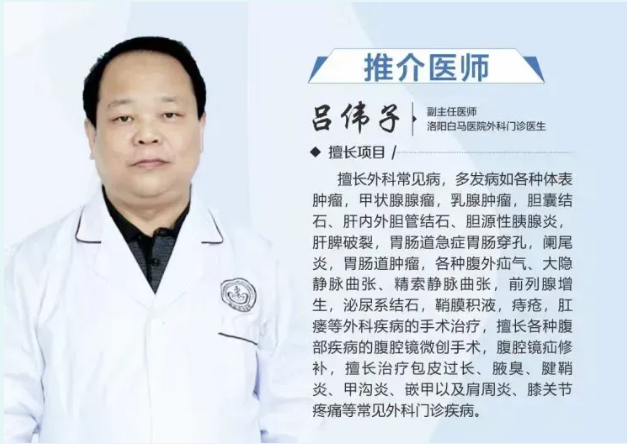

本以为只是高血压,没想到病根藏在肾脏里。我院外科吕伟子主任及其团队用微创技术,从患者体内取出了一颗7厘米的巨大肾结石。

洛阳白马医院外科(泌尿方向) 在吕伟子主任带领下,常规开展经皮肾镜、输尿管软/硬镜、腹腔镜等微创技术,对复杂肾结石、肾积水、肾血管性高血压等疾病积累了丰富经验。科室坚持以精准、安全、微创为理念,为每一位患者提供个体化诊疗方案。